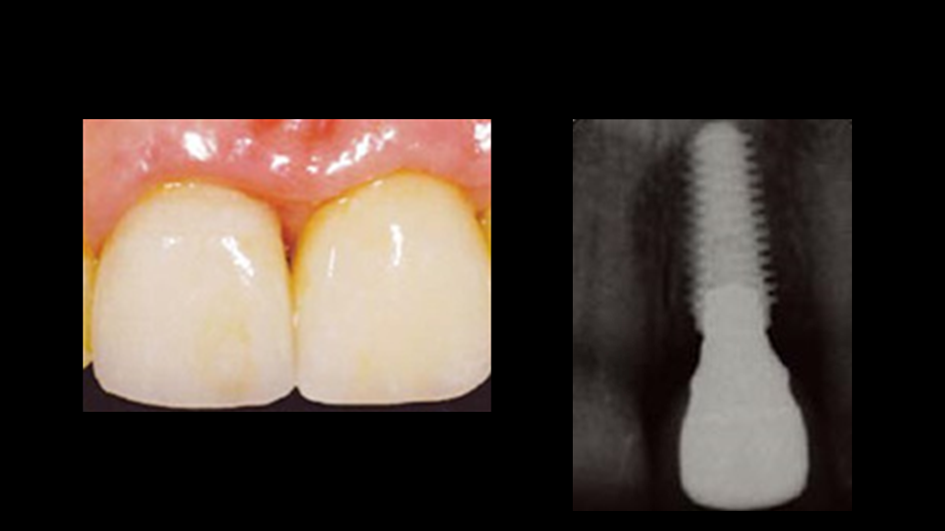

“Immediate loading of single AnyRidge implants

is a highly successful treatment modality. ”

Clinical case: Immediate post-extraction insertion of implant & immediate loading

- Courtesy of Prof. Giuseppe Luongo, Italy -

AnyRidge, immediate loading, single implant, multicenter study, maxillary anterior, Prof. Giuseppe Luongo, single replacement

AnyRidge implant system

Reference

Immediate functional loading of single implants: a multicenter study with 4 years of follow-up

/J Dent Res Dent Clin Dent Prospect 2018; 12(1):26-37 | doi: 10.15171/joddd.2018.005

https://www.ncbi.nlm.nih.gov/pubmed/29732018